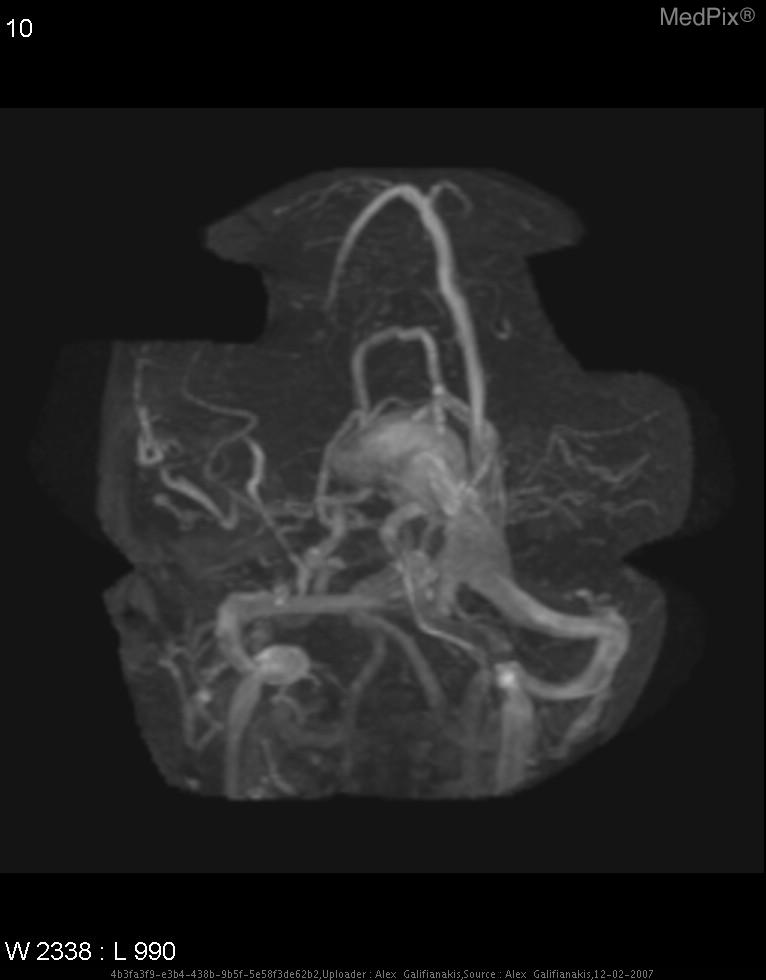

лизация мальформации

Эмболизация мальформации 113 фотографий